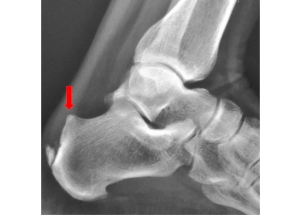

Most patients present with heel pain which can be associated with limping or swelling. The pain is most prominent while walking or other weight-bearing activities. On examination of the heel, a bump can often be appreciated as seen below. Signs of inflammation such as swelling, warmth, redness, and tenderness over the heel may also be present. An XRAY may demonstrate a bony prominence of calcaneus, as well as associated bone spurs at the Achilles tendon insertion. An MRI can demonstrate bony bodies adjacent to the calcaneal insertion of the Achilles tendon and can also evaluate for any underlying Achilles tendinopathy.